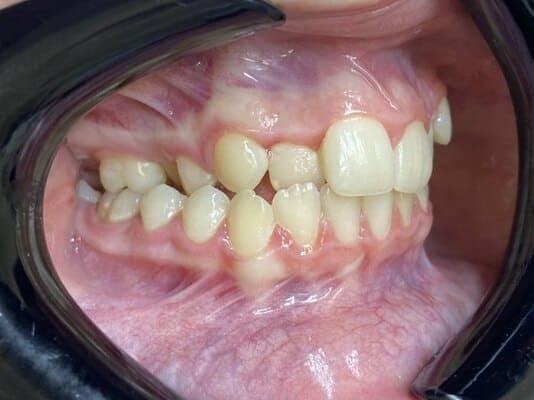

Дівчинка 4,5 років скаржилась на біль в нижньому зубі справа. В зв’язку з високою складністю процедур і значним об’ємом лікування (8 зубів) та після невдалої спроби лікування в звичайному режимі було прийнято рішення про лікування в умовах анестезіологічного забезпечення. Видаленно запалену пульпу (“нерв”) та проведено лікування каналів нижнього зуба ліворуч, цей та сусідні зуби покриті металевими коронками через значний об’єм ураження. Проліковані всі зуби, які потребували допомоги, щоб в майбутньому уникнути болю, дискомфорту та поширення інфекції. Через три години лікування дівчинка може комфортно жувати і не відчувати болю і дискомфорту.